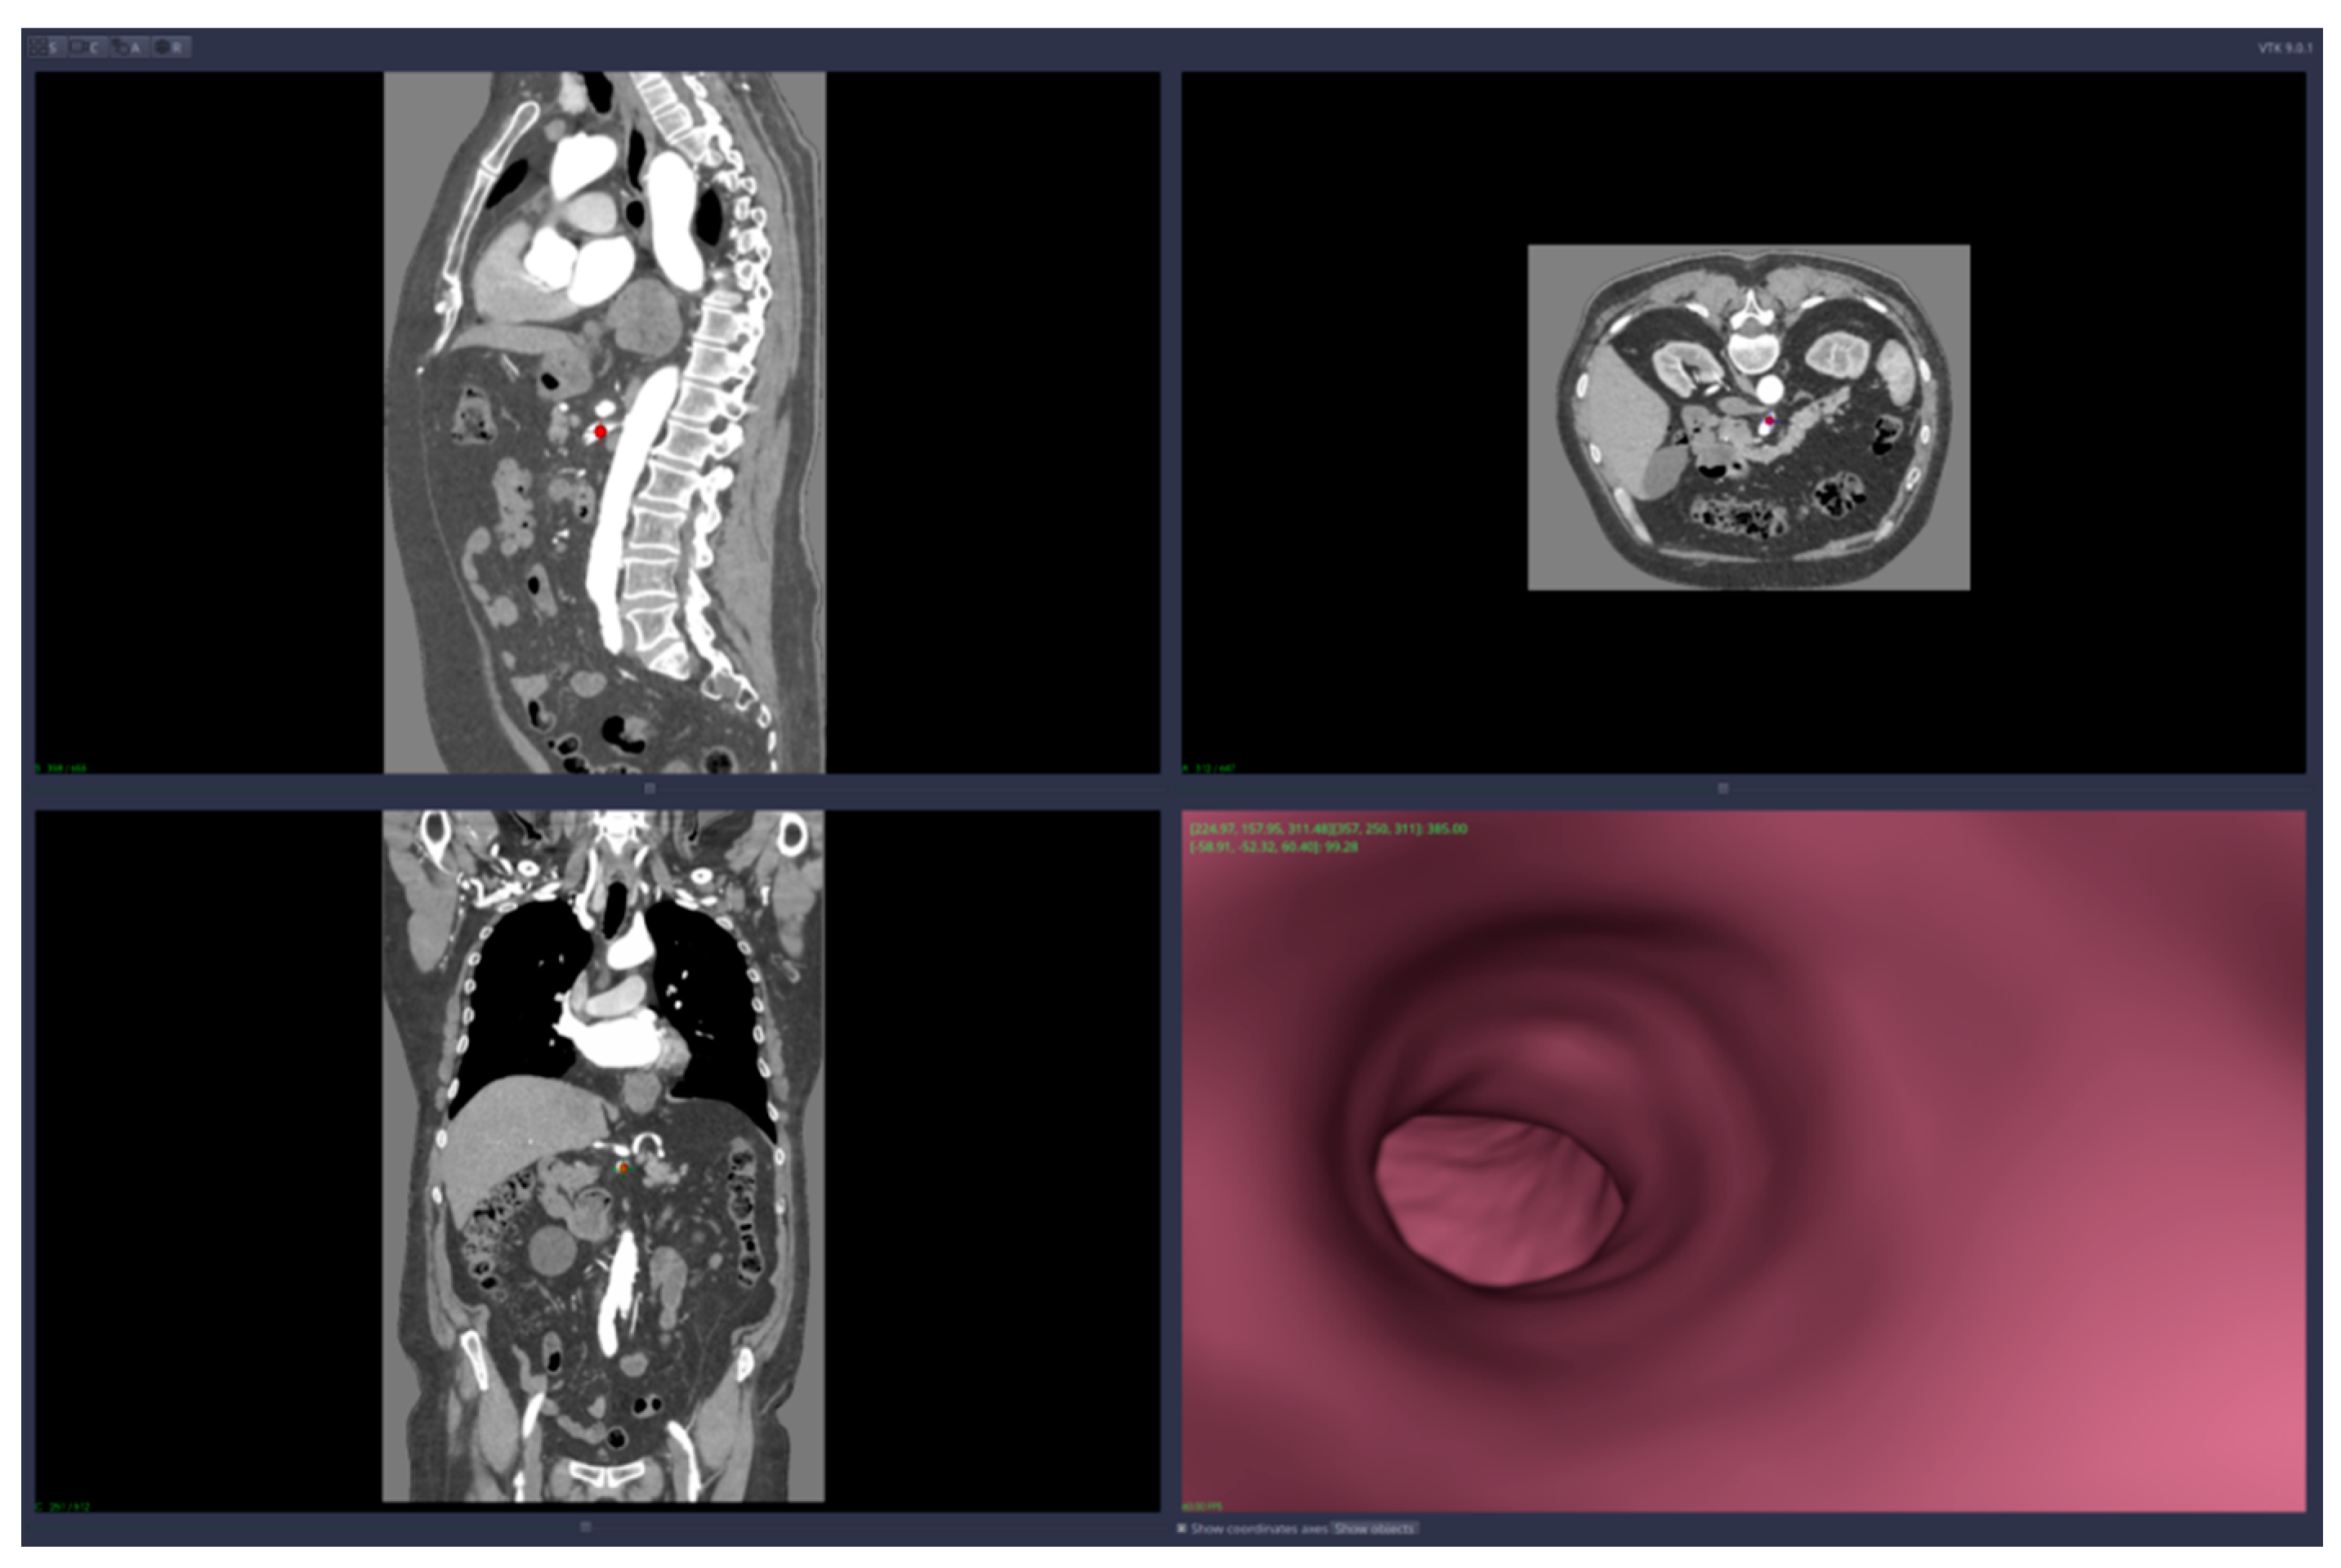

• Virtual angiography—virtual 3D navigation through the mesenteric artery and aneurysm zone (see Figure 3, Figure 4, Figure 5, Figure 6 and Figure 7)

Virtual angiography means that the user is able to navigate inside the artery using only the computer mouse device. The navigation starts from a point chosen by the user and the virtual camera is forced to remain inside the artery walls. The algorithm that implements this restriction on the virtual camera is based on collision detection and resolution directly on voxels (no segmentation is required). The path of the virtual angiography can be saved and used later, in other planning sessions.

Figure 5. Virtual angiography—“normal” zone of the mesenteric artery, after the aneurysm (direction is opposite to the blood flow).

Applsci 11 10311 g005

Figure 6. Virtual angiography—exit from the mesenteric artery into the aorta (direction is opposite to the blood flow).

Applsci 11 10311 g006

Figure 7. Virtual angiography trajectory—“procedure” started opposite to the blood flow, bottom-up, with the final point into the aorta (direction is opposite to the blood flow).